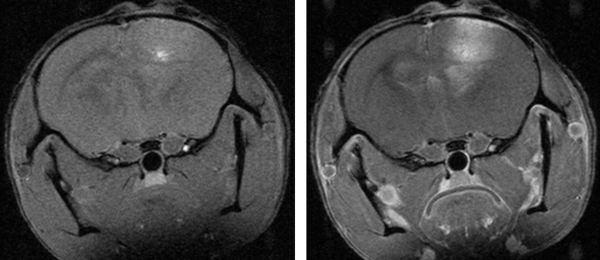

Advances In Neuro Oncology Imaging Nature Reviews Neurology